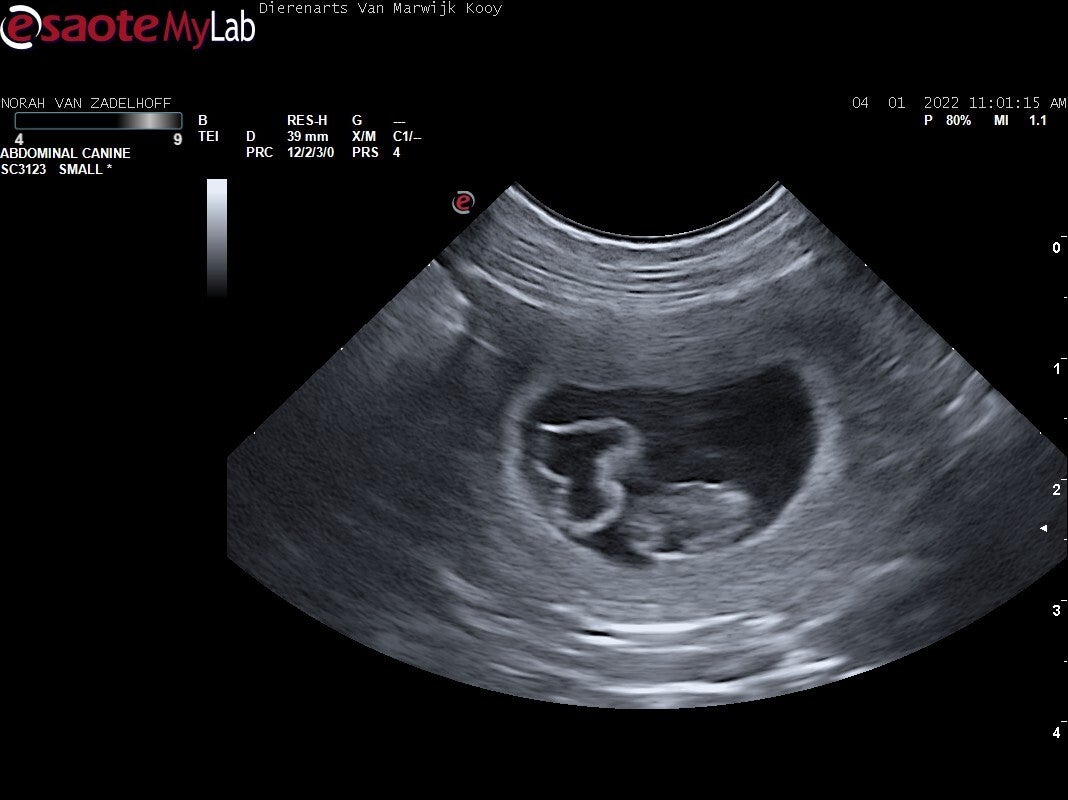

Drachtecho!

Vandaag (4 januari 2022) gingen we met Norah naar de dierenarts voor een drachtecho. We kregen te horen dat Norah drachtig was!! Hieronder kunt u enkele beelden van de drachtecho bekijken.